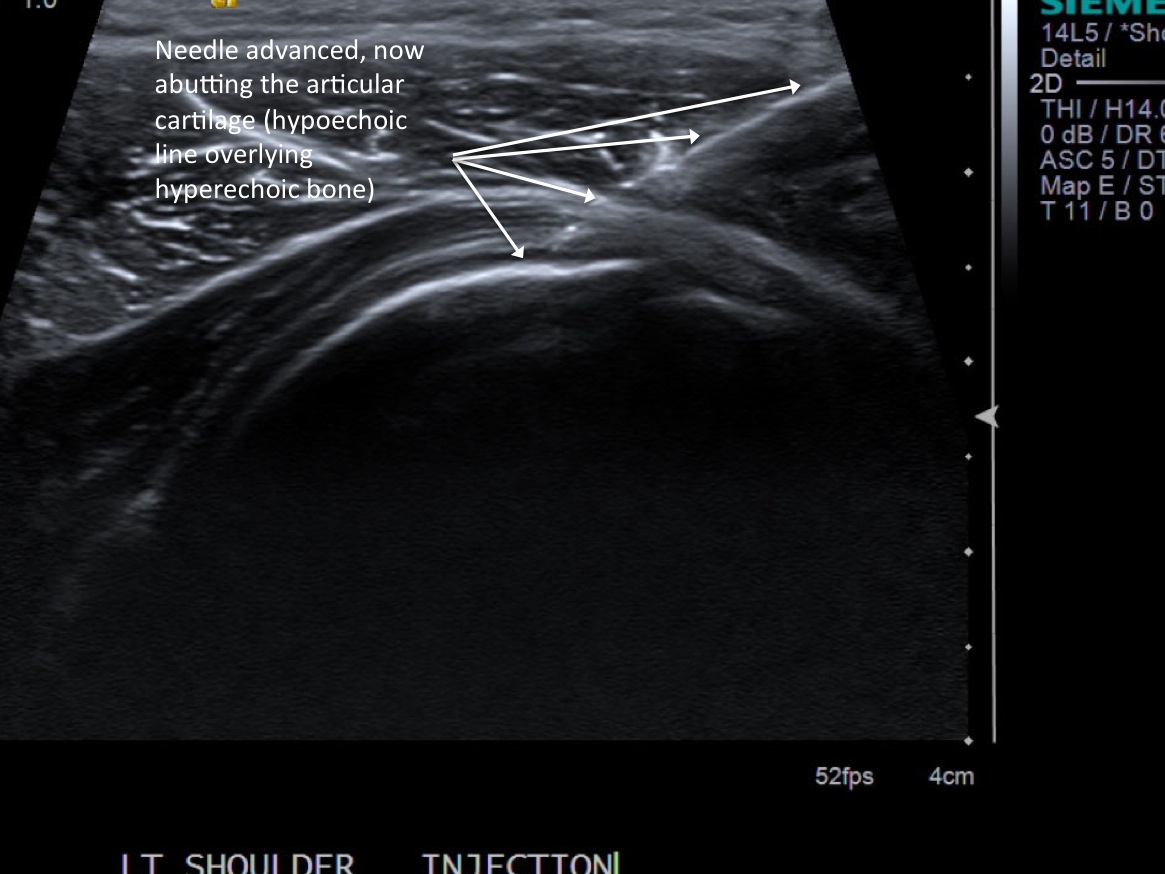

10. Advance needle under ultrasound guidance to the level of the articular cartilage (hypoechoic line).

• descriptiondescription

• At this point the needle tip is not quite at the articular cartilage and still within the overlying deltoid muscle.